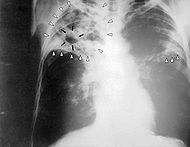

Туберкулёз

Туберкулёз (от лат. tuberculum — бугорок) — инфекционное заболевание человека и животных (чаще крупного рогатого скота, свиней, кур), вызываемое несколькими разновидностями кислотоустойчивых микобактерий — Mycobacterium tuberculosis (палочка Коха).

Чаще всего туберкулёз поражает органы дыхательной системы (главным образом лёгкие и бронхи), однако возможно поражение и других органов. Ввиду этого различают два основных вида туберкулёза: туберкулёз лёгких и внелёгочный туберкулёз.

Туберкулёз лёгких может длительное время протекать бессимптомно или малосимптомно и обнаружиться случайно при проведении флюорографии или рентгеновском снимке грудной клетки. Факт обсеменения организма туберкулёзными микобактериями и формирования специфической иммунологической гиперреактивности может быть также обнаружен при постановке туберкулиновых проб

Далее по ходу развития заболевания присоединяются более или менее явные симптомы со стороны пораженного органа. При туберкулёзе лёгких это кашель, отхождение мокроты, хрипы в лёгких, насморк, иногда затруднение дыхания или боли в грудной клетке (указывающие обычно на присоединение туберкулёзного плеврита), кровохарканье. При туберкулёзе кишечника — те или иные нарушения функции кишечника, запоры, поносы, кровь в кале и т. д. Как правило (но не всегда), поражение лёгких бывает первичным, а другие органы поражаются вторично путём гематогенного обсеменения. Но встречаются случаи развития туберкулёза внутренних органов или туберкулёзного менингита без каких-либо текущих клинических или рентгенологических признаков поражения лёгких и без такового поражения в анамнезе.